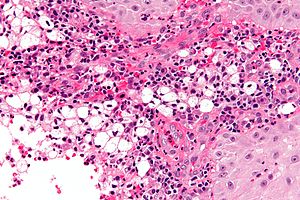

Features:[2]

- Macrophages - clear-to-foamy cytoplasm.

- Lymphocytes.

- Plasma cells.

- Warthin-Starry stain +ve (rod-shaped organisms).

- Dieterle stain +ve (rod-shaped organisms).

- S100 -ve.[5]